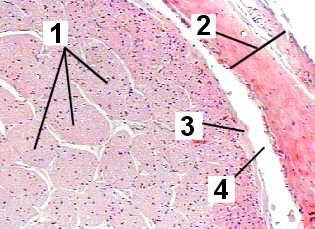

A low magnification of the optic nerve demonstrating the structures.

Fig 105-001 1. Myelinated optic nerve fibers arranged in bundles

2. Dura mater

3. Pia mater

4. Arachnoid